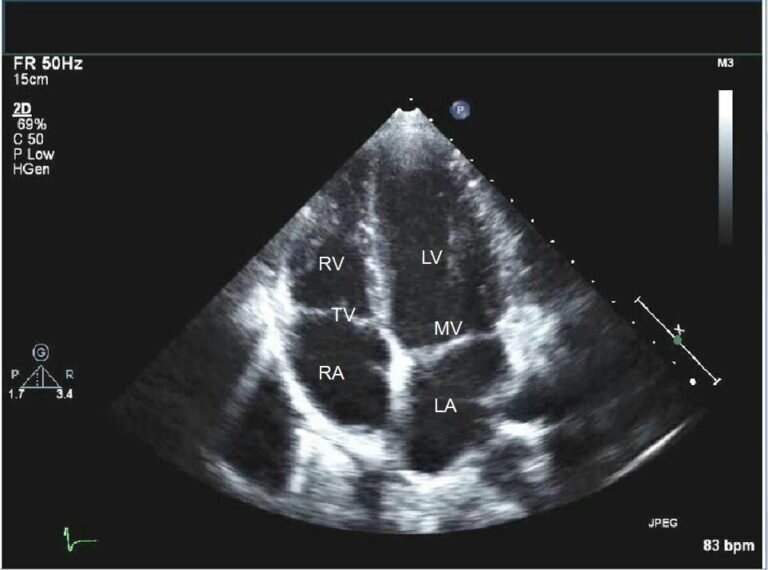

ЭХОКГ или УЗИ сердца — ультразвуковой метод, позволяющий увидеть работу сердца в режиме «онлайн».

При ЭКГ мы можем оценить и увидеть точные размеры камер сердца, крупных сосудов, отходящих от сердца (аорты и легочной артерии) и вен, подходящих к сердцу, определить толщину стенок желудочков сердца , насколько хорошо сердце сокращается и расслабляется (систолическая и диастолическая функции сердца), локальную сократимость желудочков сердца (участки сердечной мышцы, плохо сокращающиеся или совсем не работающие из-за ишемии или перенесенного инфаркта миокарда), оценить работу клапанов сердца, измерить скорость кровотока на каждом из клапанов, выявить пороки сердца.